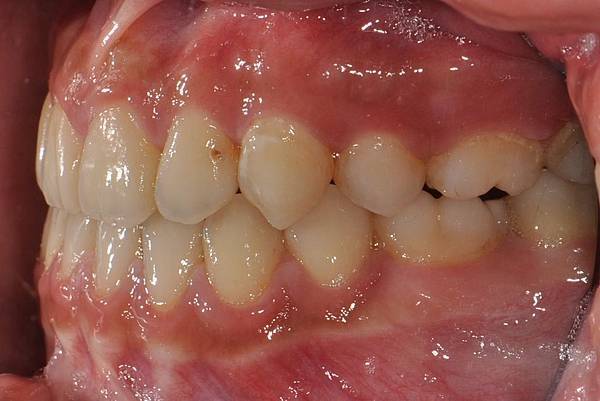

戽斗下唇突出改善案例

本案例因為考量到患者下唇突出

便建議拔除上下四顆小臼齒將

下唇內收

也改善了

前牙錯咬

的問題~

治療前/治療後

-以上案例由林昇進醫師提供